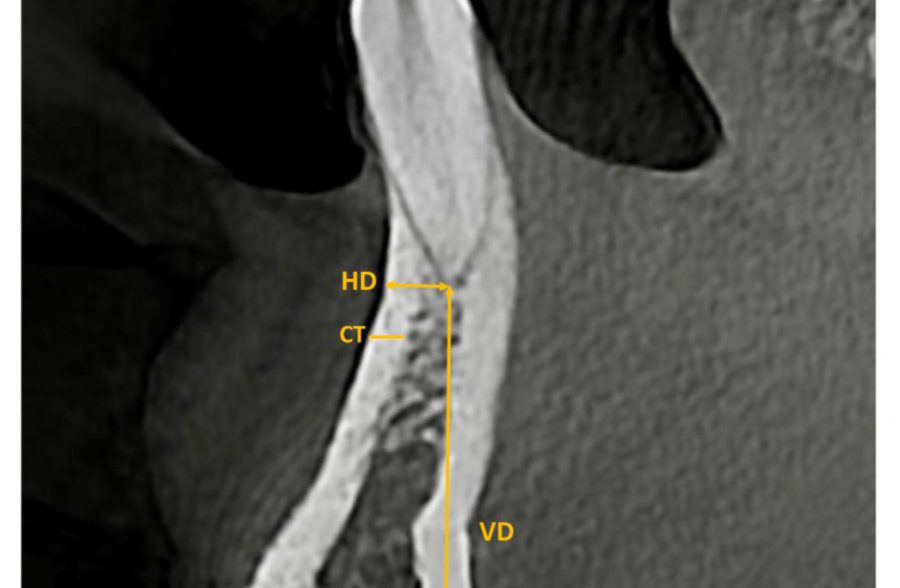

Bone quality and quantity of the mandibular symphyseal region in autogenous bone grafting using conebeam computed tomography: a crosssectional study